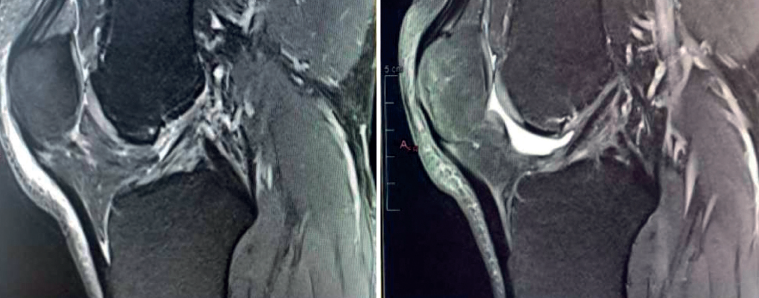

We now know from the histological study of ACL remnants after rupture that the ligament has some intrinsic capacity for spontaneous healing, as evidenced by the presence of vascular buds, nerve endings and cells with healing capacity in the remnant tissue(3). Further evidence of this self-repairing capacity can be found in the good functional results published in some patients treated on a conservative basis, especially older individuals with lesser physical demands(4)(Figure 1).

The main indication for primary ACL repair is in patients with high-grade complete or partial tears corresponding to types 1 or 2 of the original Shermanclassification(7), i.e. in avulsions of the femoral insertion (type 1) or in proximal tears leaving 75-90% of the distal ligament intact (type 2). In any case, good quality of the remaining tissue is essential. It should be noted that the incidence of tears of this kind appears to be greater in individuals over 35 years of age(7). This is not a problem, given that the incidence of re-rupture following ACL repair is higher in younger patients under 21 years of age(8,9).

With regard to the timing of surgery, the operation is ideally performed within 6 weeks of the injury(10,11,12), although good results have also been published repairing chronic tears in which the torn ACL stump heals over the posterior cruciate ligament (PCL)(13,14).